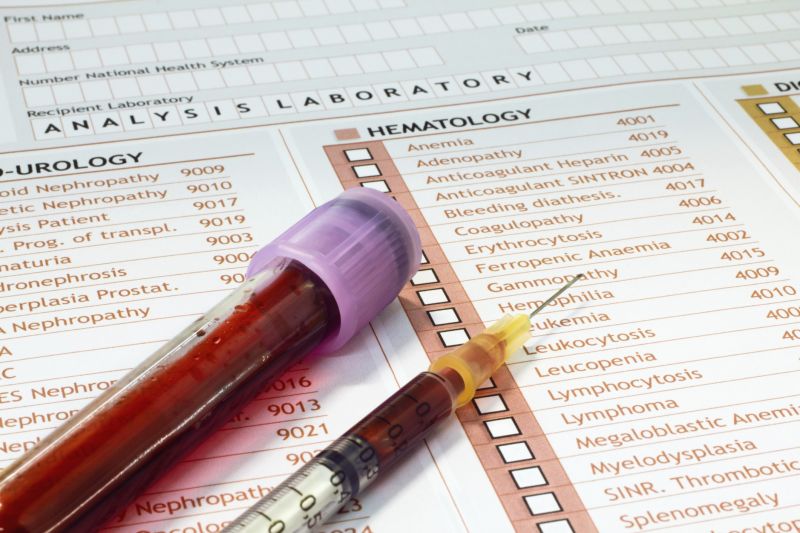

Niedobór żelaza i niedokrwistość z niedoboru żelaza mogą dotyczyć każdego. To powszechne schorzenia występujące na całym świecie i dotykające zarówno mężczyzn, jak i kobiety, osoby młode, jak i starsze [1]. Niedobór żelaza jest najbardziej rozpowszechniony wśród kobiet w okresie przedmenopauzalnym, wśród kobiet w ciąży oraz dzieci w wieku poniżej 5 lat [2]. W Europie niedobór żelaza dotyka do 33% kobiet w okresie przedmenopauzalnym, do 77% kobiet w ciąży oraz do 48% dzieci [2].